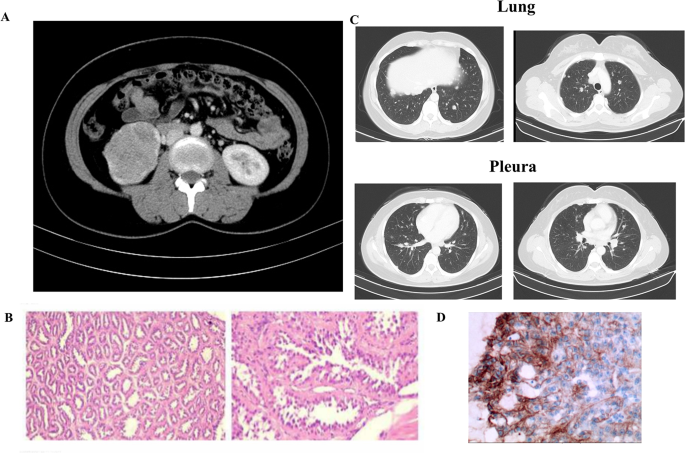

Considering the positive expression of PD-L1, the patient was immediately treated with sintilimab and anlotinib in February 2021 (Fig. 3). Two months after treatment, a reduction in the lesion, almost to the level of a partial response, was observed. The patient’s disease was stable until November 2021. The patient subsequently experienced pleural effusion, and the other lesions were stable. The patient was switched to pembrolizumab and axitinib combined with intraperitoneal chemotherapy, and the disease was considered stable in April 2022. A partial response was observed in October 2022. The patient is still in follow-up.

The patient had new metastatic lesions after surgery but showed a response during immunotherapy. At 3 months after surgery, CT revealed metastatic lesions in both lungs and the pleura. The lung lesions were stable until November 2021 after sintilimab and anlotinib treatment. With the switch to pembrolizumab and axitinib, the lung lesion showed a partial response in October 2022